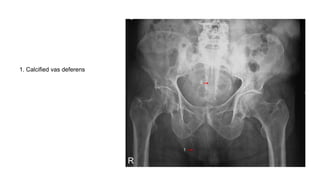

1. Calcified vas deferens